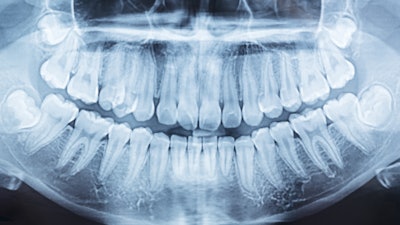

Assessing bone mineral density (BMD) on the sides of the jaw known as the mandibular ramus via panoramic dental x-rays may help flag patients at risk for osteoporosis. The study was recently published in the Journal of Oral and Maxillofacial Surgery.

Osteoporosis, which commonly occurs in postmenopausal women, significantly reduces bone density and increases the risk of fractures. Cortical bone, which is the biggest calcium deposit in the human skeleton, is principally affected by conditions like osteoporosis. Since the cortical bone can be seen on panoramic radiography, this area of the lower jaw canal may be helpful in assessing BMD.

To characterize and compare changes in the cortical areas of the mandibular canal, the panoramic x-rays from 52 normal osteopenic and osteoporotic postmenopausal women over the age of 40 were assessed. All of the women underwent osteoporosis risk assessment by dual-energy x-ray absorptiometry (DEXA).

Of these women, 26 were normal, 19 were osteopenic, and eight were osteoporotic. In this cross-sectional study, black pixel intensity on the radiography was used to measure BMD of the mandibular canal cortices.

Among the groups, considerable differences were seen in the percentage of black pixels in the mandibular ramus. For the normal group, the average percentage of black pixels was 3.19% (±0.65). For the osteopenic and osteoporosis groups, the average percentages were 2.78% (±0.65) and 2.35% (±0.65), (p = 0.015), respectively, the authors wrote.